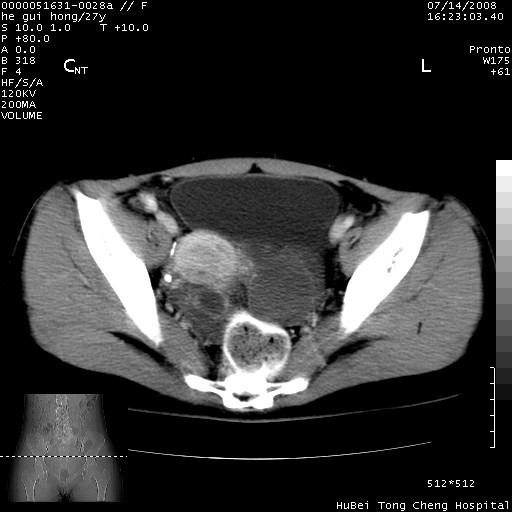

以下是引用杀毒软件在2008-7-20 8:03:00的发言:[br]支持双侧卵巢囊腺瘤可能性大!

以下是引用zjzjr在2008-7-20 13:36:00的发言:[br]双侧附件囊腺瘤可能性大!